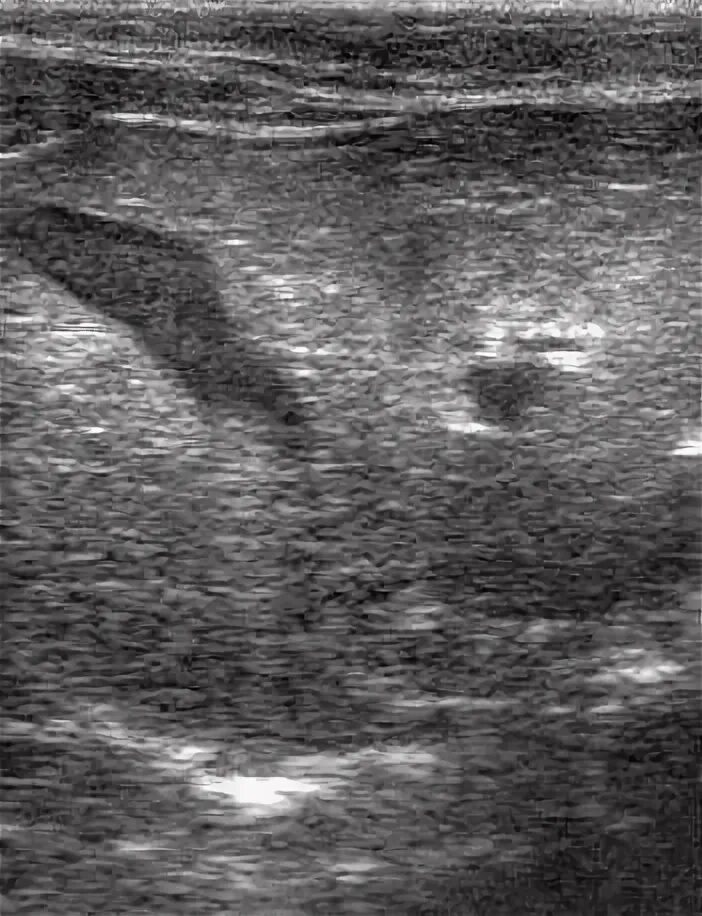

Липидоз печени